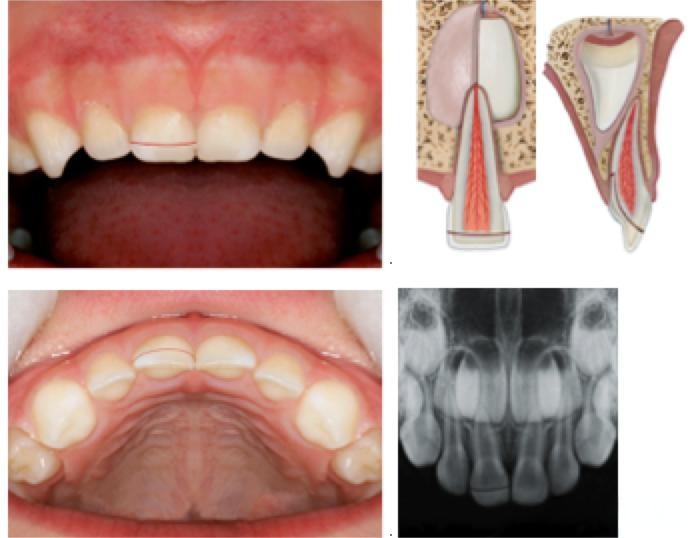

冠根折涉及牙髓(乳牙)

A 基本描述:

一种涉及牙釉质,牙本质和牙骨质的牙体缺损,并暴露牙髓。

折裂线的定位:折裂涉及牙齿的冠部和牙根,并且处于水平或斜切面中。X射线检查通常仅揭示折裂的牙冠部分而不是根尖部分。

描述

折裂线涉及牙釉质,牙本质和牙骨质的牙体缺损,暴露牙髓

视诊

冠折裂延伸到龈缘下方。冠折裂成两个或更多个片段,其中一个是移动的

放射学检查 根尖向的折裂折通常不可见

放射推荐 咬合片